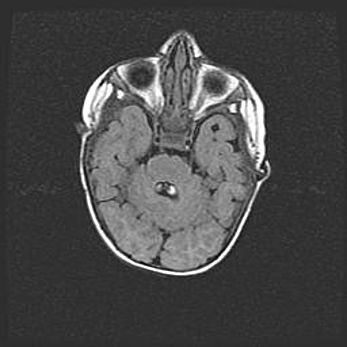

Церебральная ишемия II.

Возраст: 5 дней

Вес: 3400 г

Пол: женский

Окружность головы: 35 см

Срок гестации: 39 недель

Церебральная ишемия – это заболевание, характеризующееся недостаточностью (гипоксией) либо полным прекращением (аноксией) снабжения мозга кислородом по причине закупорки одного или нескольких сосудов. Это приводит к  что метаболическим расстройствам различной степени тяжести в тканях головного мозга, развитию коагуляционных некрозов и гибели нейронов.